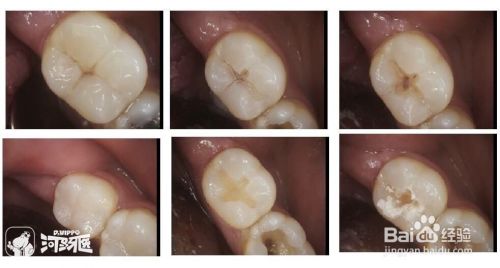

一个牙齿产生了龋洞,充填后与充填体相连接的牙体组织还有可能发生龋坏,我们称为“继发龋”,牙齿的其他部位也会发生龋坏,我们称为“再发龋”。

龋洞进行治疗时,充填材料在凝固时的体积収缩,材料被腐蚀或黏接剂溶解等原因都会造成洞壁和充填材料之间出现微小的渗漏,如治疗中患者不能配合医生,导致血液及唾液的污染,使充填材料不能很好地与洞壁密合,更容易造成边缘渗漏,导致继发龋。

因此,规范的治疗技术、抗龋材料的使用及患儿的配合,都能大大降低继发龋的发生。一旦有了继发龋或再发了龋齿,就要去除原有的充填物和龋坏的病变组织,重新充填。相关阅读@补牙详细过程